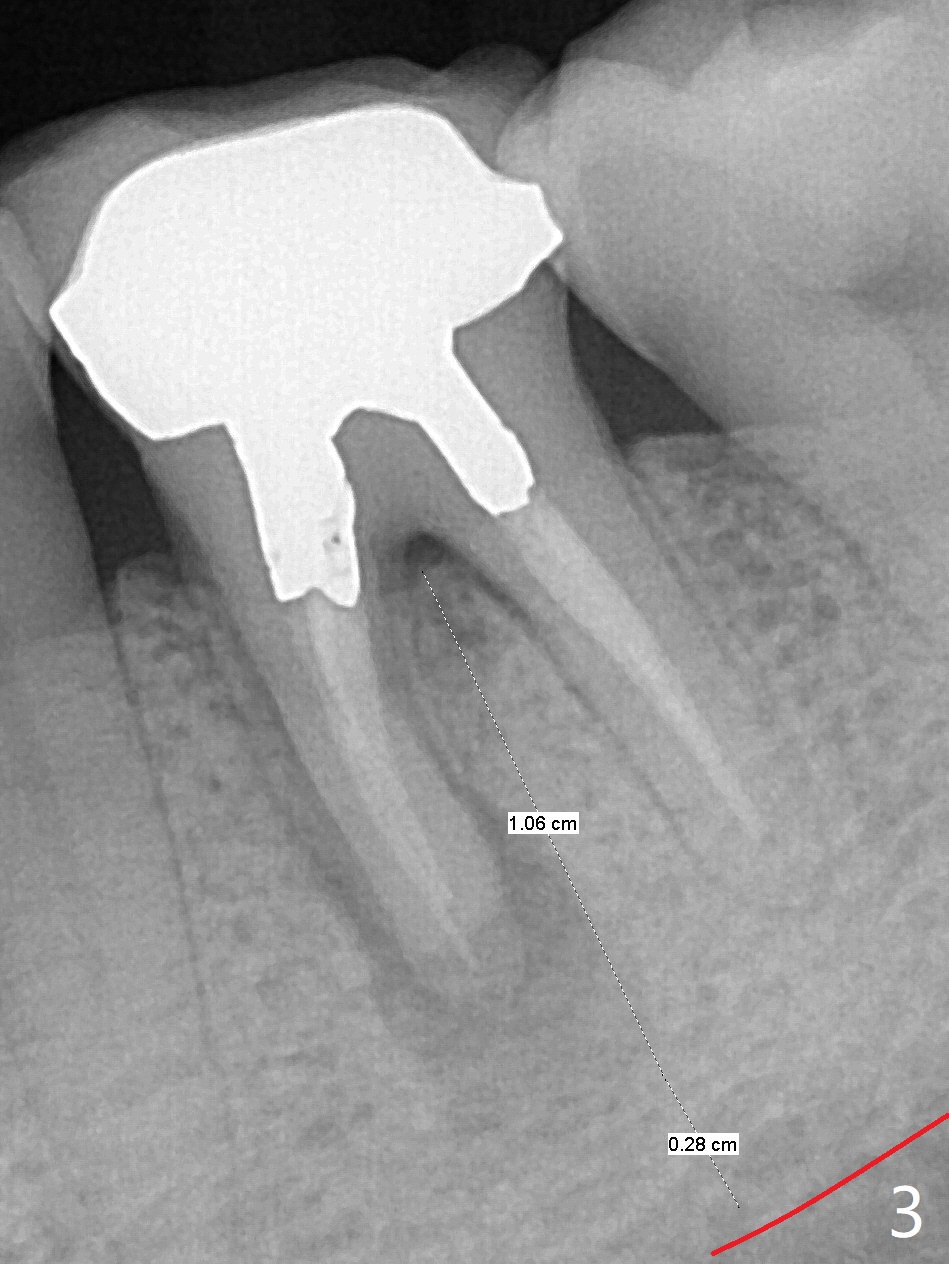

A 53-year-old man has had pain with chewing gums at #19 for 3 years (Fig.1). While a 7x17 mm implant was immediately placed at #30 six years earlier, a 5x17 mm one will be inserted at #19 as lingual as possible to reduce buccal thread exposure (Fig.2). The whole tooth will be extracted before osteotomy in the septum, since the roots in the sockets do not help free hand osteotomy unless the crown breaks off during extraction. Initial depth will be 14 mm. Use Tatum 17 mm drills. Drills are more likely deviated to the mesial socket with large PARL (Fig.1 *). Use visual acuity to correct deviation as early as possible. Pack sticky bone into the mesial bony defect for repair. Take photos of #19 and 30 for buccal recession and fistula if present. It is safe to place a 11 mm long bone level implant (Fig.3,5). It would be ideal to establish initial osteotomy as indicated by the red arrow (Fig.4).